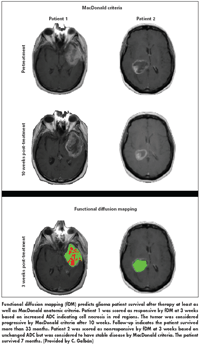

The functional diffusion maps segment the tumor into three categories: red voxels for tumor volumes where the apparent diffusion coefficient (ADC) increased significantly following treatment, blue voxels where ADC decreased significantly, and green voxels where ADC was unchanged.

“We are interested in the volume fraction of increasing ADC in the tumor, which is encoded as red voxels on the fDM,” Dr. Galbn said.

The ability of functional brain mapping to differentiate among responders and nonresponders after 3 weeks of treatment was similar to results produced with the conventional MacDonald criteria after 10 weeks (see Figure). Dr. Galbn added, “fDM has significant potential as an imaging biomarker for early cancer treatment response.”

Using functional mapping data gathered 3 weeks after the initiation of therapy, patients who had a volume fraction of red that made up more than 5% of the tumor volume survived five times longer than patients who had a volume fraction of red that was less than 5% of tumor volume, he said. The next step is a multicenter clinical trial to validate this single site prospective trial (Hamstra et al: J Clin Oncol 26:3387-3394, 2008).